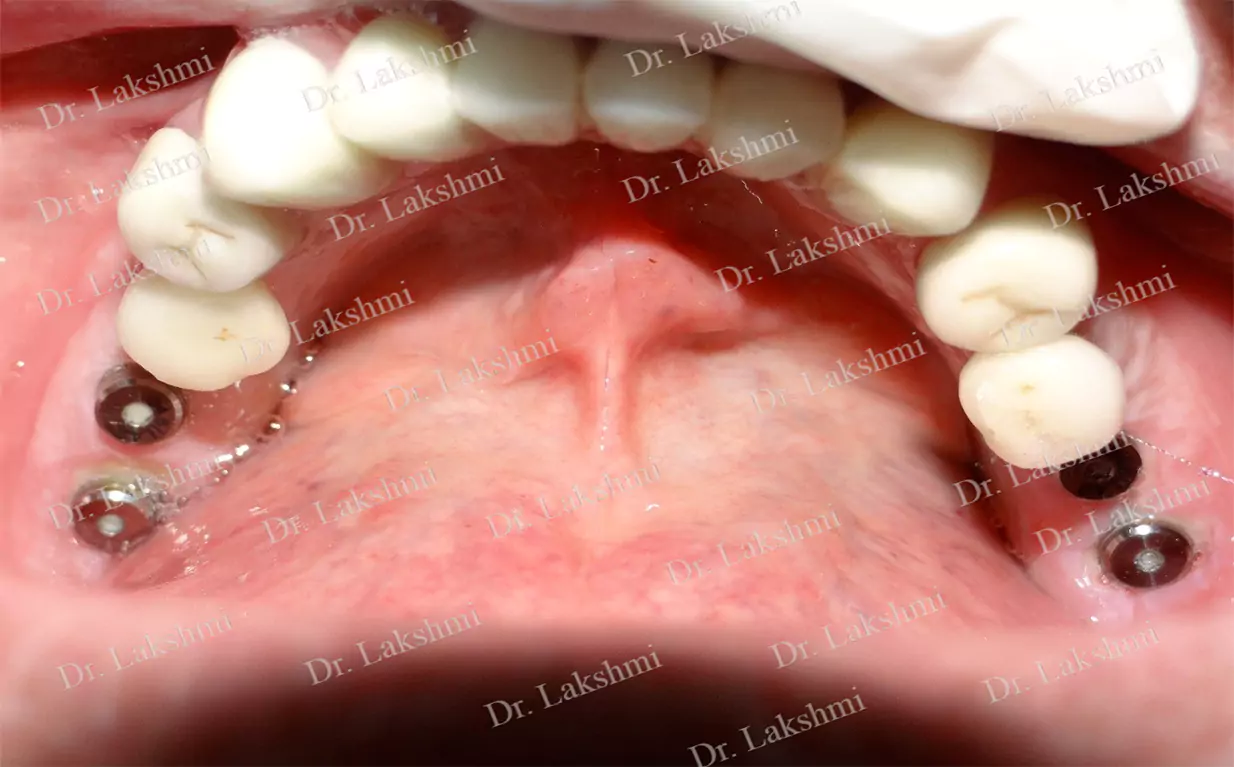

Replacement of All Teeth: Replacement of all teeth can be done either by the placement of implant supported dentures or by the placement of multiple unit bridges placed over implants.

Treatment Duration: 2 stage dental implants: The replacement is completed in 2 stages which are spread over an interval of minimum 3 months. The first stage involves the placement of the implant and requires one to two sittings,Temporary Crowns will be given to the patient. The second stage involves the placement of the artificial tooth (Permanent crown).

1 stage dental implant: Requires just one stage for the placement of the implant and crown(Permanent Crown).